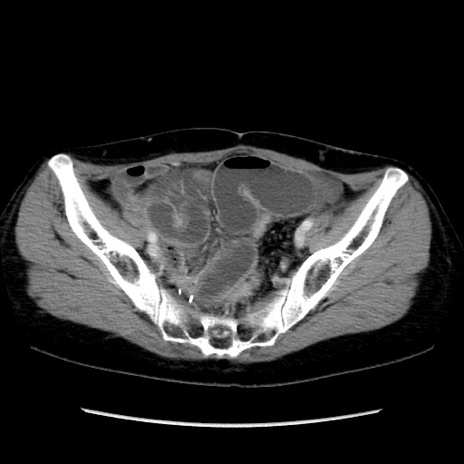

冠状断像

【症例】40歳代 女性

【主訴】上腹部痛、嘔気・嘔吐

【現病歴】約9時間前頃から急に上腹部痛、嘔気、嘔吐が出現。改善しないため救急要請。

【既往歴】子宮頚癌(広汎子宮全摘術、放射線療法)、腸閉塞

【身体所見】腹部:平坦、軟、腸雑音亢進、上腹部を中心に腹部全体に圧痛あり。

【データ】WBC 8400、CRP 0.03